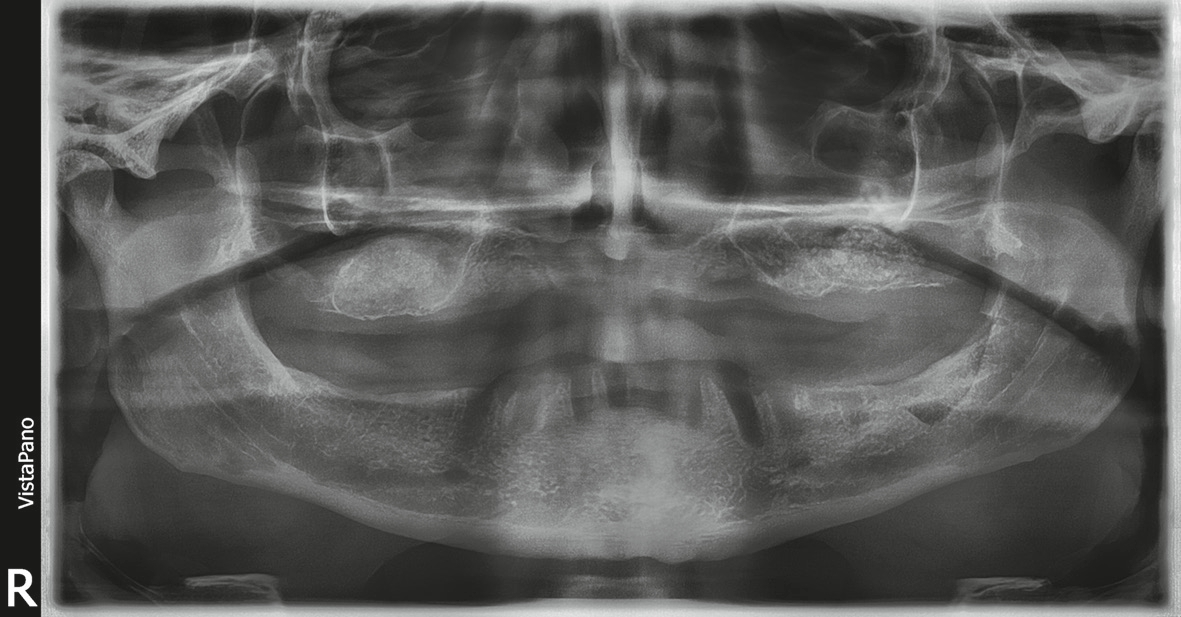

- DVT-Analyse mit Röntgenschablonen, die das zuvor erarbeitete prothetische Ziel radiologisch sichtbar machen.

- Virtuelle Planung der möglichen Implantatpositionen und Evaluation, ob eine festsitzende Versorgung ohne Beckenkammaugmentation durchführbar ist. Die Analyse ergab, dass eine Versorgung im Oberkiefer mit acht Implantaten und im Unterkiefer mit sechs Implantaten für ein festsitzendes Zahnersatz-Konzept zwar implantologisch anspruchsvoll, aber durchführbar wäre. Daraufhin wurden die optimalen Implantatpositionen sowohl in Bezug auf den verfügbaren Knochen als auch das prothetische Ziel definiert und in der Planungssoftware (coDiagnostiX) festgelegt (Abb. 3-5).